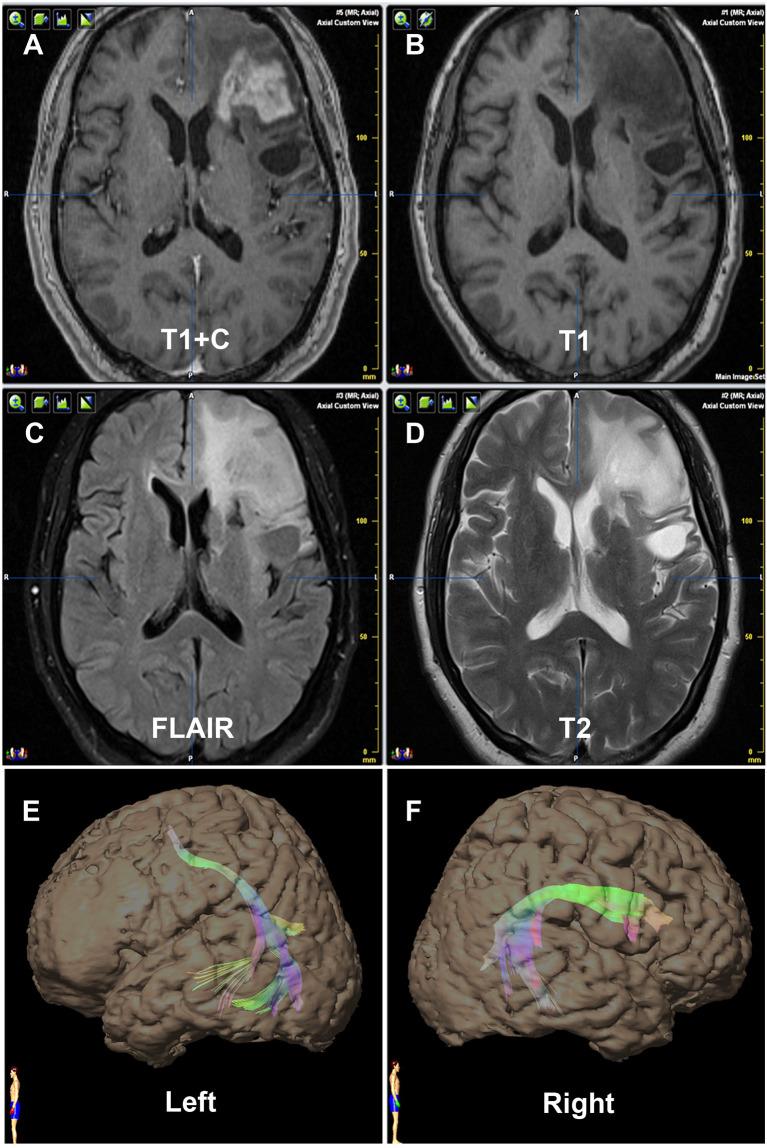

Language lateralization is unique to humans, so clarifying dominant side is helpful for removing gliomas involving language areas. This study investigated the arcuate fasciculus (AF) reconstructed by diffusion tensor imaging-based tractography (DTT) in predicting language lateralization in patients with low-grade gliomas. Wada test was performed to determine the language Dominant Hemisphere (DH) and the Contralateral Hemisphere. DTI data [1.5-T magnetic resonance imaging (MRI)] was used to reconstruct AF by two independent operators using a DTT method. Fiber number, volume, and fractional anisotropy (FA) of bilateral reconstructed AF were measured. Lateralization indexes (LIs), including Number Index (NI), Volume Index (VI), and FA Index (FI), were accordingly calculated by mean values. A total of 21 patients with WHO Grade II gliomas in the left hemisphere were included. Every patient received a successful Wada test and reconstruction of bilateral AF. DTT metrics of reconstructed AF, such as fiber number, volume, and FA, showed significantly asymmetric between hemispheres. All the LI (NI, VI, and FI) values were statistically higher in the DH determined by the Wada test. No discrepancy was found between the prediction using the cutoff values of DTT metrics and the results of WADA test. The Kappa values were 0.829, 0.696, and 0.611, indicating NI and VI as more reliable predictor than FI although FI itself may also be feasible. Compared with the Wada test, we consider that DTT of AF is a non-invasive, simple, relatively accurate, and feasible method in predicting language lateralization in patients with low-grade gliomas.

语言侧化是人类独有的,因此明确优势侧有助于切除累及语言区的胶质瘤。本研究调查了基于扩散张量成像纤维束示踪(DTT)重建的弓状束(AF)在预测低级别胶质瘤患者语言侧化中的作用。进行Wada试验以确定语言优势半球(DH)和对侧半球。使用1.5-T磁共振成像(MRI)的DTI数据由两名独立操作人员采用DTT方法重建AF。测量双侧重建AF的纤维数量、体积和分数各向异性(FA)。相应地通过平均值计算包括数量指数(NI)、体积指数(VI)和FA指数(FI)在内的侧化指数(LI)。共纳入21例左半球WHO二级胶质瘤患者。每位患者均成功进行了Wada试验和双侧AF重建。重建AF的DTT指标,如纤维数量、体积和FA,在半球间显示出明显的不对称性。在Wada试验确定的DH中,所有LI(NI、VI和FI)值在统计学上更高。使用DTT指标的临界值进行的预测与WADA试验结果之间未发现差异。Kappa值分别为0.829、0.696和0.611,表明NI和VI比FI是更可靠的预测指标,尽管FI本身也可能可行。与Wada试验相比,我们认为AF的DTT是一种预测低级别胶质瘤患者语言侧化的非侵入性、简单、相对准确且可行的方法。